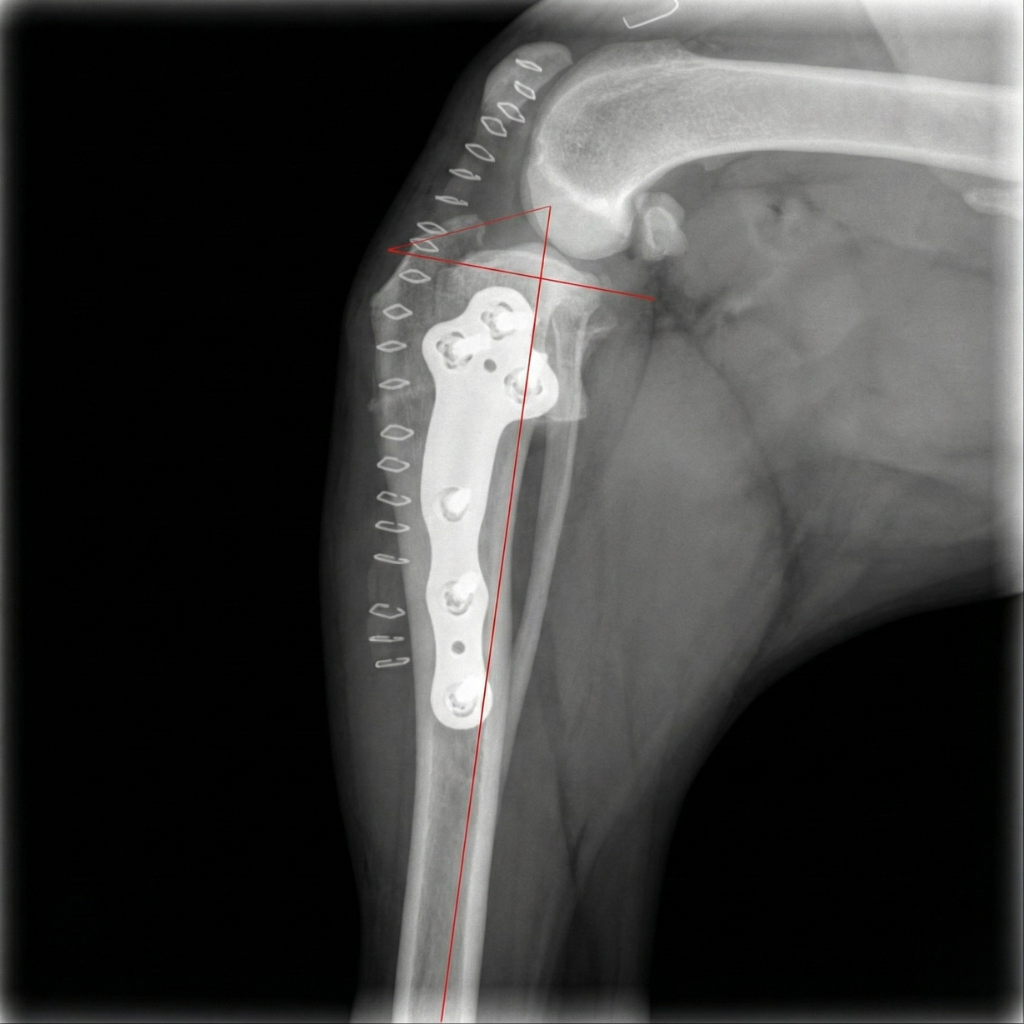

drkorani-tplo